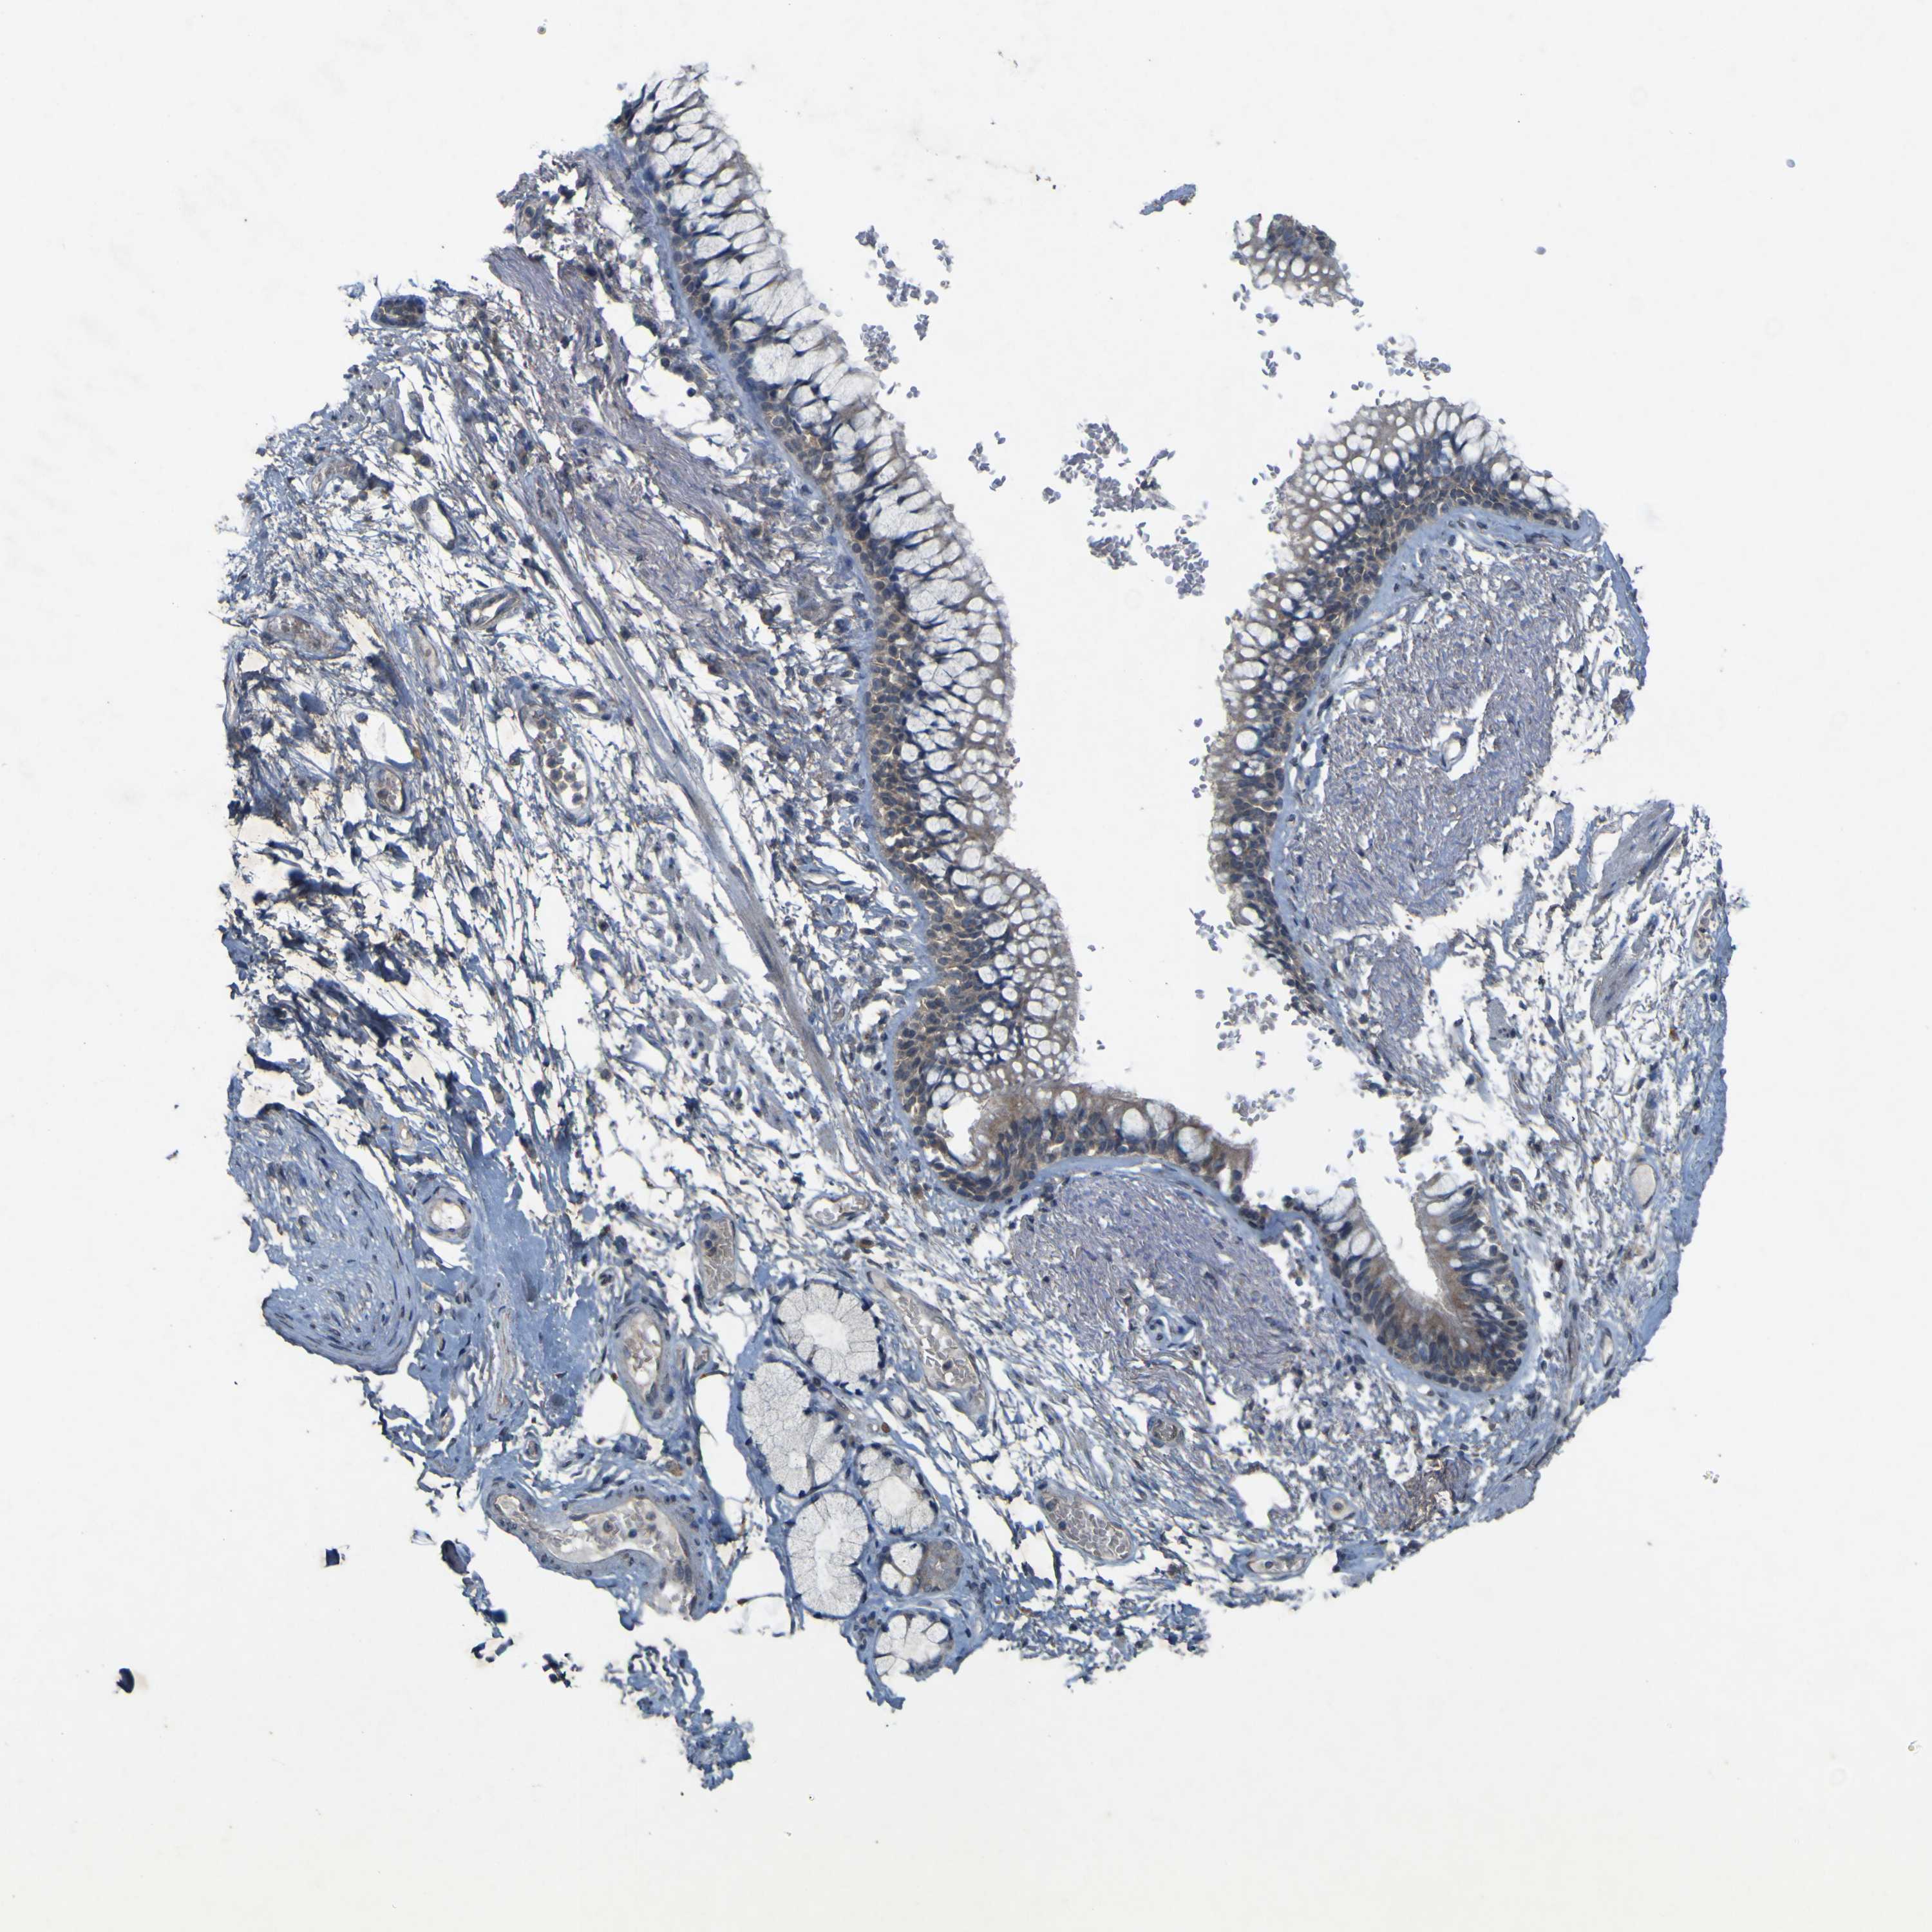

PRKCG